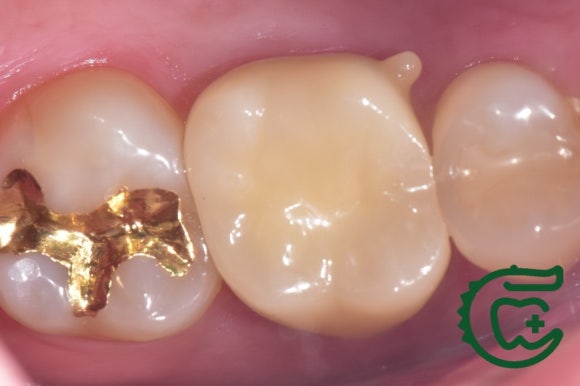

타치과에서 재신경치료를 받으시던 도중에

저희 치과로 오셨습니다.

깔끔하게 신경치료를 마무리 해드렸습니다.

어금니 신경치료의 마무리는

튼튼한 지르코니아 크라운입니다.